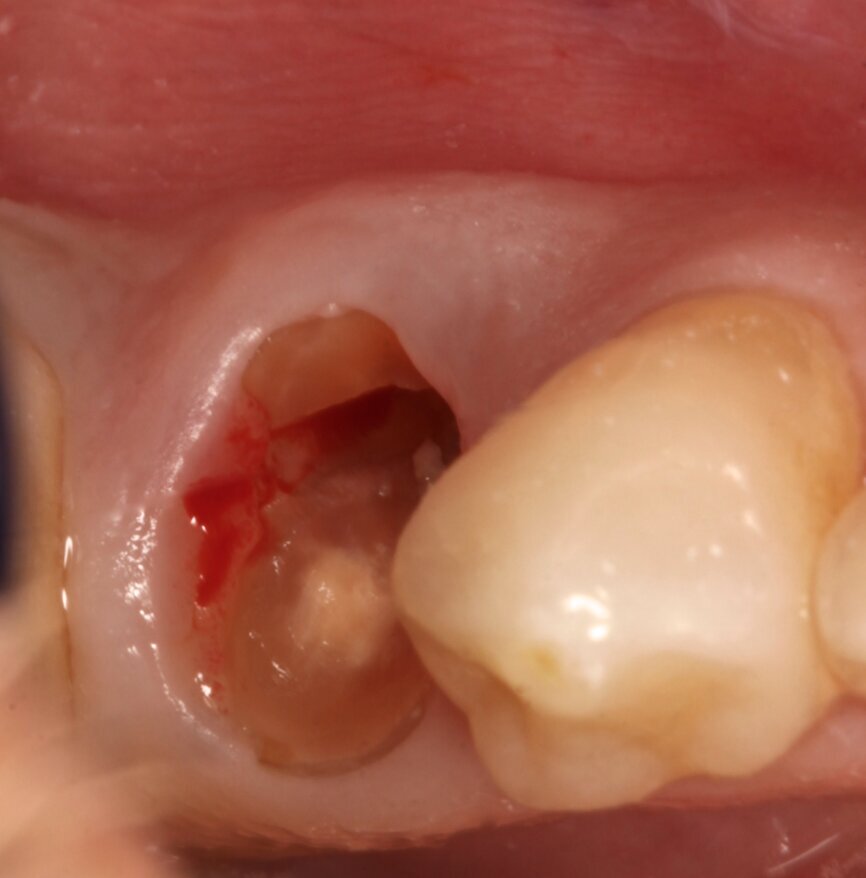

Fig. 1a: Initial situation: apical radiograph (a), intra-oral view (b) and CT scan (c).

Fig. 1b: Initial situation: apical radiograph (a), intra-oral view (b) and CT scan (c).

A healthy, non-smoking, 40-year-old male patient presented with a mandibular left first premolar with a fractured root. The root had previously been treated endodontically, three years before suffering a bone level transversal fracture (Figs.1a & b). The patient had already received several implants to replace some of his lost teeth over the previous nine years. The missing mandibular premolar could be easily seen and was one of his complaints. The patient had moderate aesthetic expectations, high functional demands and little time to come to the appointments.

After analysing the computed tomography (CT) scan on BTI Scan II software (BTI Biotechnology Institute; Fig. 1c), the root was not considered to have the minimum criteria for retaining a crown, or a post and core and crown. As the bone availability, bone density and remaining buccal bone were considered to be ideal, implant therapy was immediately considered.

This CT scan was taken three years before the root fractured. As there was no infection related to the root and sulcus probing, all around the remaining root and all the way down to bone contact showed no socket alteration—a Type I socket was diagnosed—it was decided not to irradiate the patient further. This CT scan data, supported by the clinical examination, was considered reliable, despite the three years that had passed.